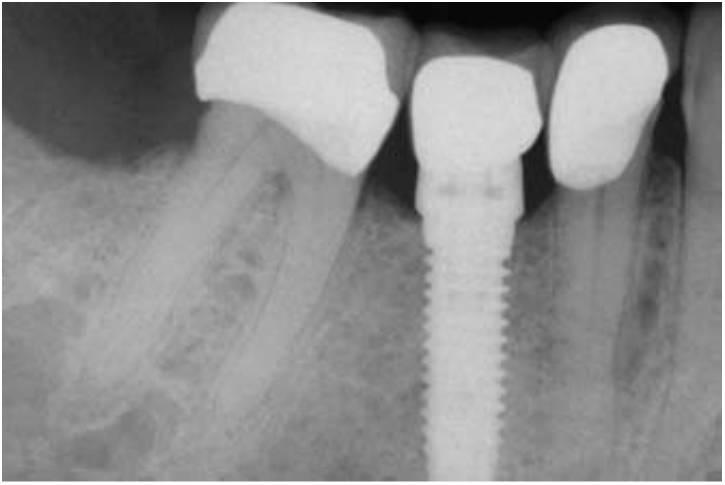

El estrés global sobre todo el sistema del implante puede reducirse aumentando el área sobre la que está aplicada la fuerza. El método más efectivo para aumentar el área de la superficie de soporte del implante consiste en aumentar el número de implantes de soporte de la prótesis (fig. 4-32). Por ejemplo, estudios previos de Bidez y Misch han demostrado que la fuerza distribuida sobre tres pilares da como resultado un estrés menos localizado en la cresta del hueso que con dos pilares. Este estudio se aplica únicamente a los implantes que están ferulizados conjuntamente. De ahí que, cuando las fuerzas están aumentadas, debería reducirse el número de pónticos y aumentar el de pilares de implantes, en comparación con la planificación de tratamiento para un paciente ideal con factores de fuerza mínimos.

Una longitud excesiva del implante no es tan crítica en la interfase ósea de la cresta, si no más bien para la estabilidad inicial y la cantidad global de interfase hueso-implante. Un aumento de la longitud proporciona también una mayor resistencia a fuerzas de torque o transversas cuando se atornillan los pilares en su sitio. En cualquier caso, la longitud excesiva hace bien poco para reducir el estrés que se produce en la región transósea alrededor del implante en la cresta del reborde durante la carga oclusal. Una longitud excesiva del implante no es un método tan efectivo para disminuir el estrés ocasionado por los factores de fuerza.

Por otra parte, con una gestión biomecánica incorrecta, los implantes más cortos pueden tener medias de fracaso más altas después de la carga. Por tanto, el plan de tratamiento inicial debería emplear implantes de por lo menos 12 mm de longitud. De una manera ideal, los huesos de tipo más blando requieren implantes más largos que el hueso denso. El área de la superficie de cada implante esté directamente relacionada con la anchura del implante. Los implantes con forma de raíz más ancha tienen una mayor área de contacto óseo que los implantes estrechos (o de diseño similar), como resultado del incremento de la circunferencia de sus áreas de contacto óseo. Cada aumento de 0,25 mm en el diámetro del implante puede aumentar aproximadamente el área de la superficie entre un 5 y un 10% en un implante de cuerpo cilíndrico. El aumento de la anchura ósea puede estar indicado para aumentar el diámetro del implante de 1 mm cuando los factores de fuerza son mayores de lo ideal. Además se ha sugerido que un aumento en el diámetro del implante puede ser más efectivo que escalonar los implantes para reducir el estrés.